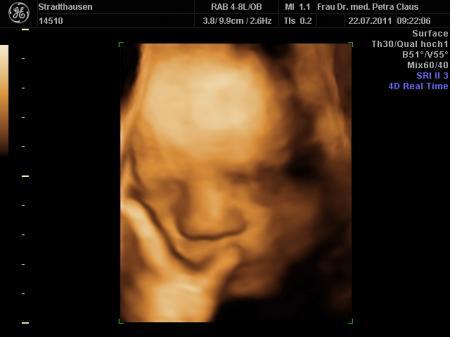

komme grad von der VU und bin ja so ein bisschen megahappy. Endlich hab ich meinen Kleinen wieder im 3D ultralschall gesehen und der war heut vielleicht in Action

...schon beim CTG hat er rumgekaspert, fleißig gegen den Schallkopf getrampelt und sich immer weggedreht, zum Schluss noch nen schönen Schluckauf....voll süß

...alles soweit unauffällig. Dann beim Ultraschall ging es richtig los...Schnute auf, Schnute zu.....wir haben uns köstlich amüsiert. Jedenfalls hat er seinen kleinen Wachstumsrückstand wieder gut aufgeholt, hoffentlich bleibt alles so schön und gesund.

Maße bei 32+4

Gewicht: 2150 gramm

Länge: 42-43 cm....

anbei noch ein paar Bildchen.